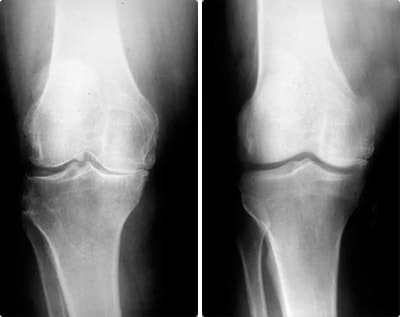

Las lesiones pueden variar en complejidad, pero se pueden agrupar en dos tipos: musculares y articulares. Esguinces, desgarros, osteoartritis crónica. Los riesgos son inevitables si no te proteges a tiempo.